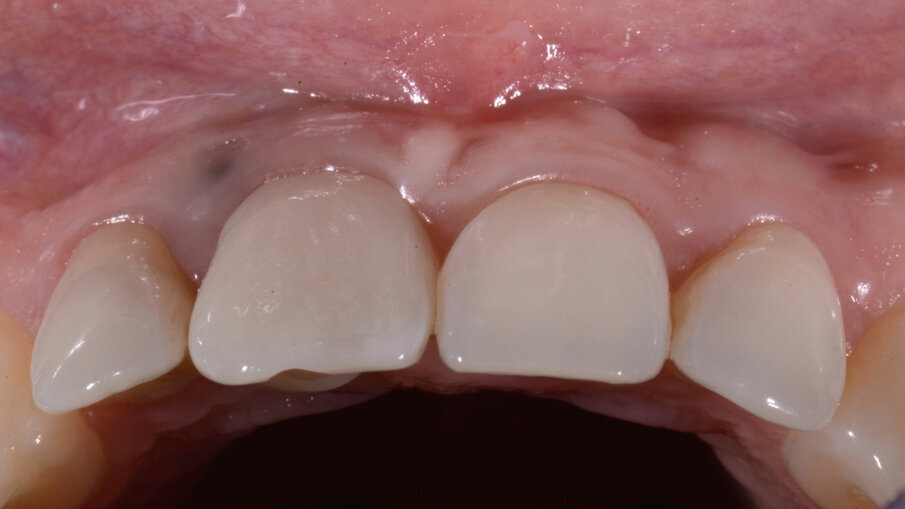

Come noto, per raggiungere un risultato ottimale nei casi estetici, è necessario che vi sia una certa armonia tra tessuti molli e manufatti protesici: ciò significa che le papille interdentali, le parabole gengivali, gli assi dentali, la dominanza degli incisivi centrali devono essere ben bilanciati tra di loro (Fig. 1)

Fig. 1_Composizione estetica anteriore ideale.

Trascorsi quattro mesi, ad avvenuta osteointegrazione dell’impianto, il condizionamento dei tessuti appariva ottimale sia in termini di qualità dei tessuti sia in termini di volume rigenerato. I profili gengivali erano perfettamente armonici e naturali grazie al provvisorio (Fig. 29). A questo punto, dopo avere svitato il provvisorio dall’impianto, ho copiato con lo scanner intra-orale la posizione delle papille e della parabola gengivale. In tal modo, creando la cosiddetta “Maschera gengivale”, ho condiviso con il software le informazioni morfologiche necessarie per realizzare i manufatti protesici definitivi (Figg. 30, 31).

Il dente progettato è stato fresato utilizzando un cubetto di disilicato di litio forato e a bassa translucenza per meglio mascherare il grigiore del titanio del Tbase. Dopo avere scolpito la tessitura superficiale, il dente è stato lucidato utilizzando gomme con diverso grado di abrasività al fine di diversificare le diverse aree del dente rendendolo più naturale e in armonia con i denti vicini (Figg. 33-35). In corrispondenza della gengiva aderente è evidente un tatuaggio relativo alla posizione della pregressa fistola che potrà essere eliminato in qualsiasi momento qualora la paziente lo richiedesse. Le immagini ad 1 anno mostrano la stabilità nel tempo dell’ottimo risultato ottenuto (Figg. 36, 37).